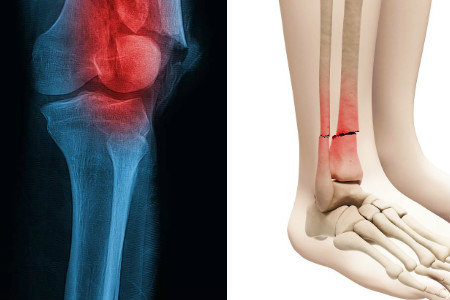

如果我们的腿部骨折了,那我们需要学会一些辅助性的恢复方法,这样才能帮助我们尽快恢复起来,缩短恢复的时间。腿部按摩是一种比较常用的方式。通过腿部的肌肉按摩,能促进腿部血液的流通,从而达到排毒排泄的效果。如果允许的话,也可以试着做一些腿部的舒展运动,这样能锻炼到腿部的肌肉,加速腿部的恢复。